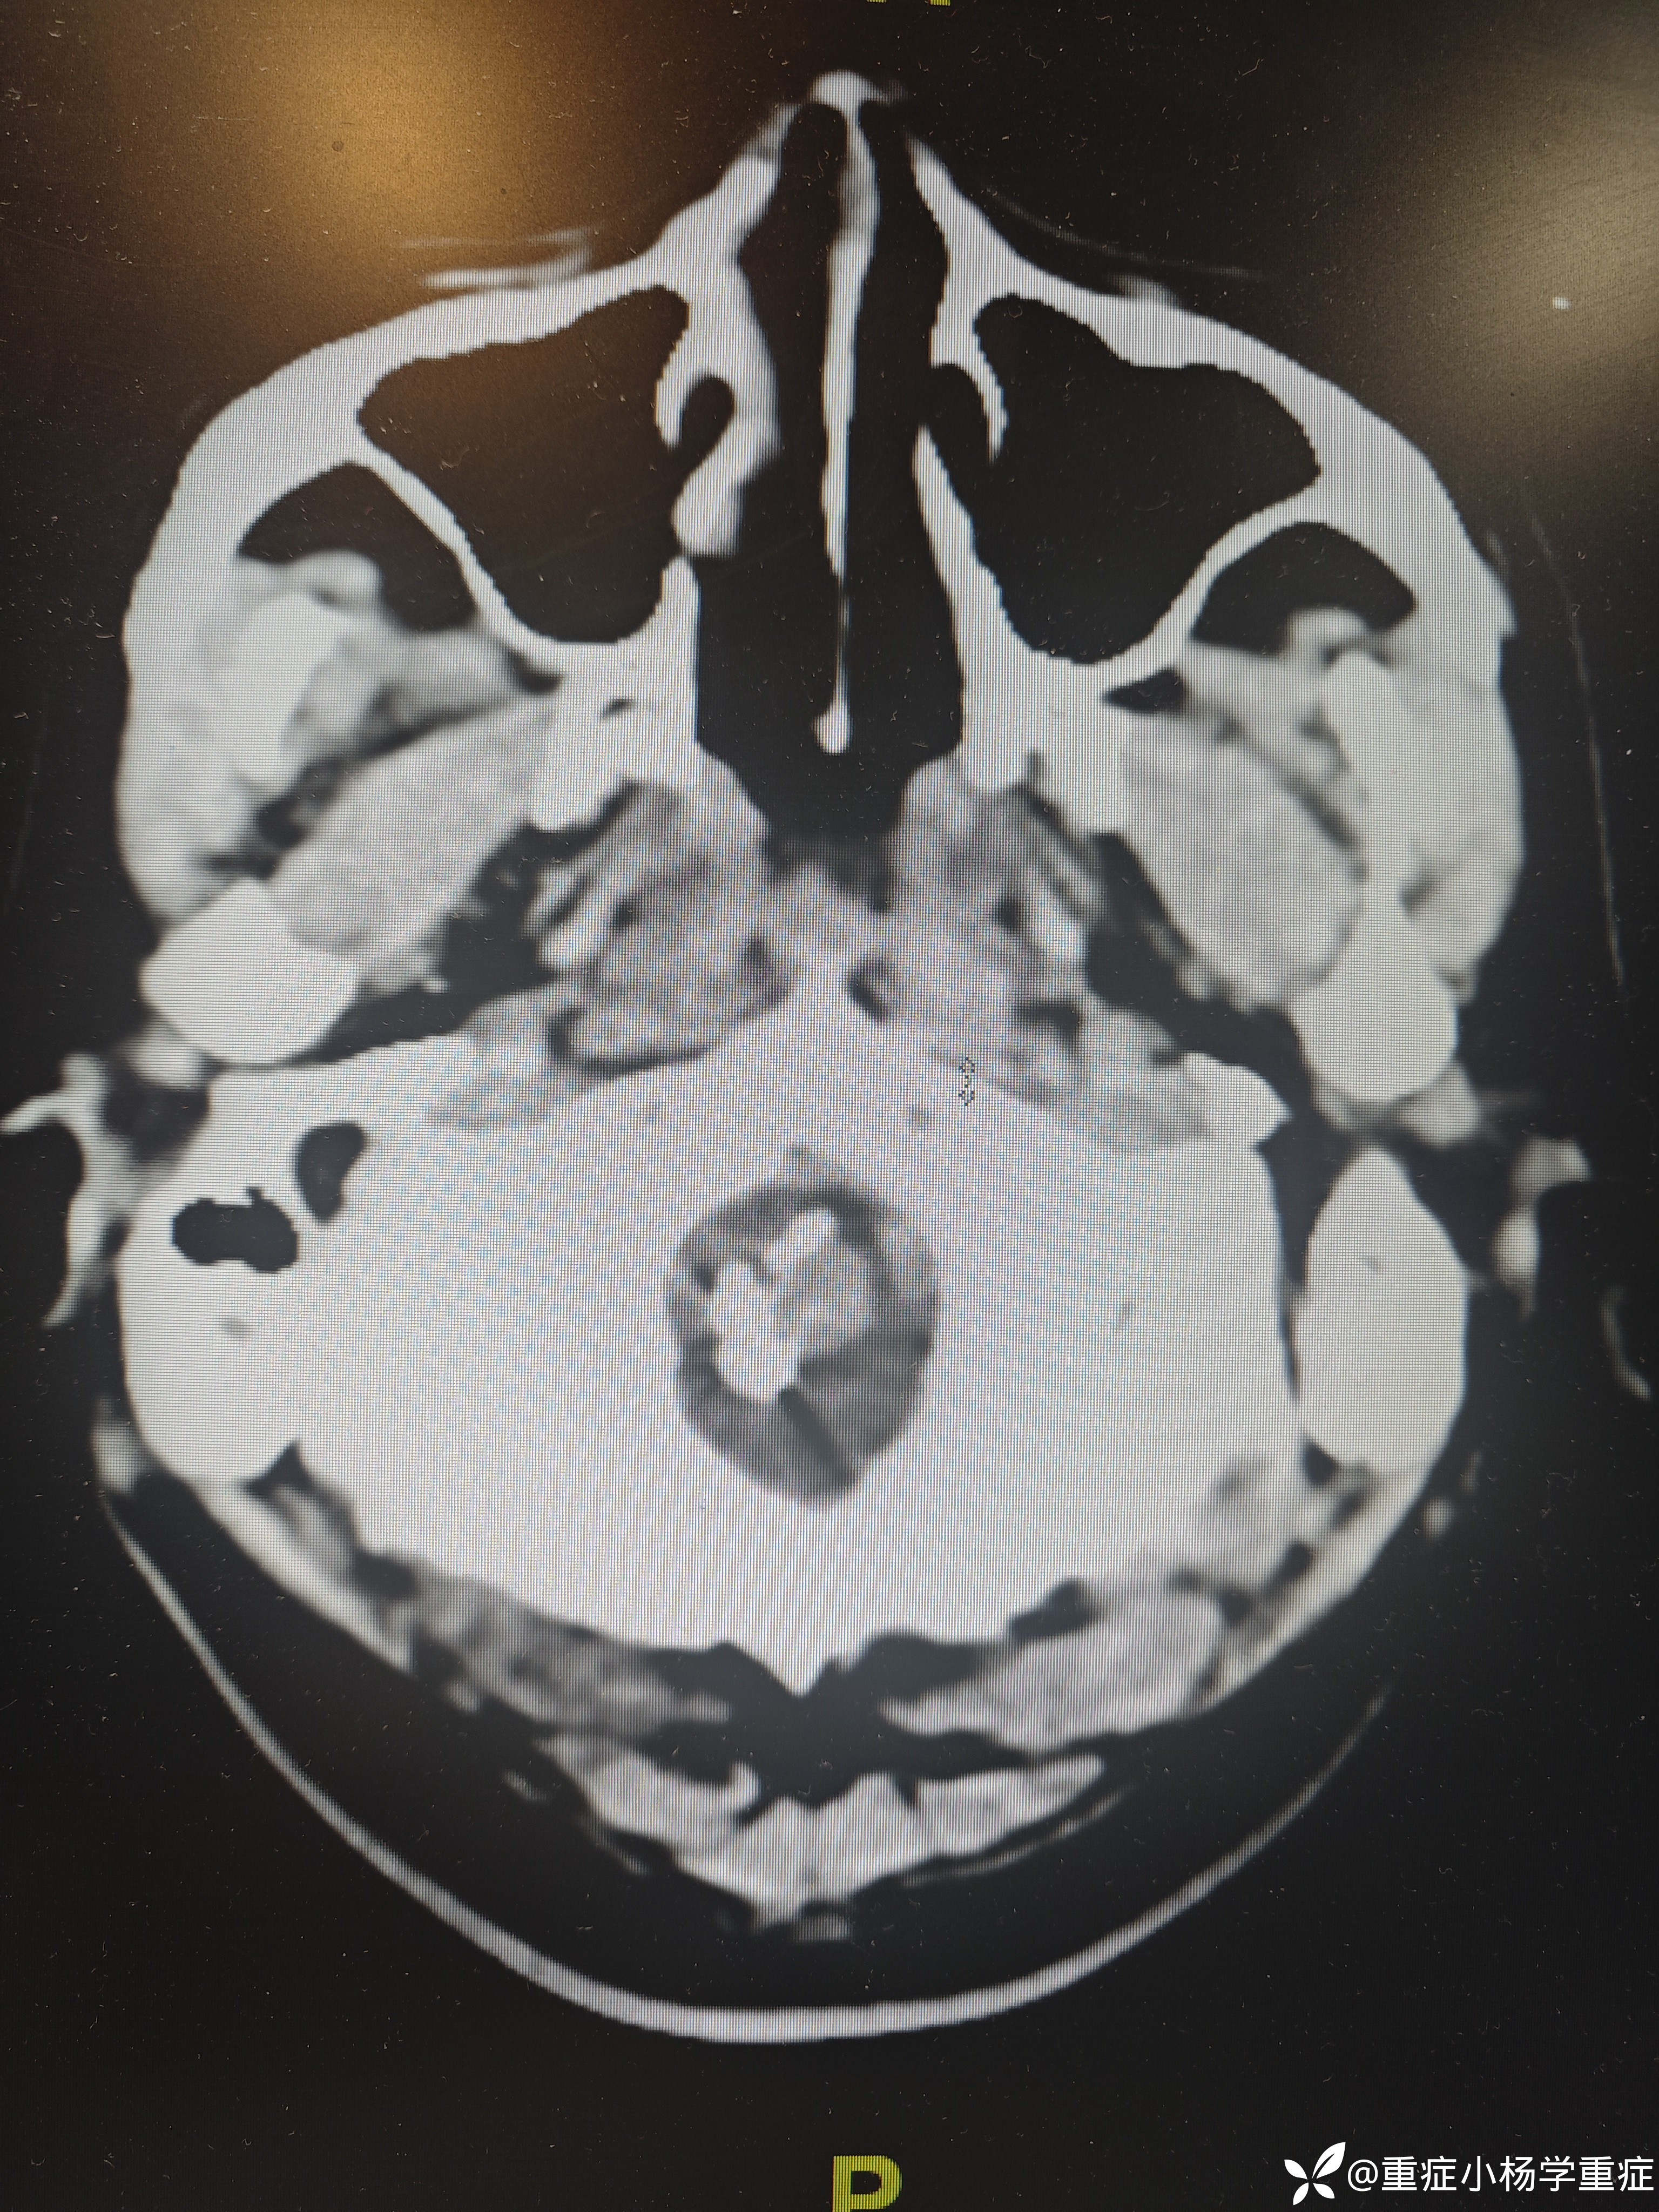

飞跃迷雾1 达人已点赞因“代:脑出血术后2月余,痰多伴呼吸困难1小时”入院。因头痛至医院检查ct提示蛛网膜下腔出血,后完善CTA提示脑血管畸形,至省内医院行介入栓塞后出现脑梗塞,考虑压迫延髓导致呼吸功能损伤,术后第二天予以气切,后出现四肢瘫痪,近期ct如下